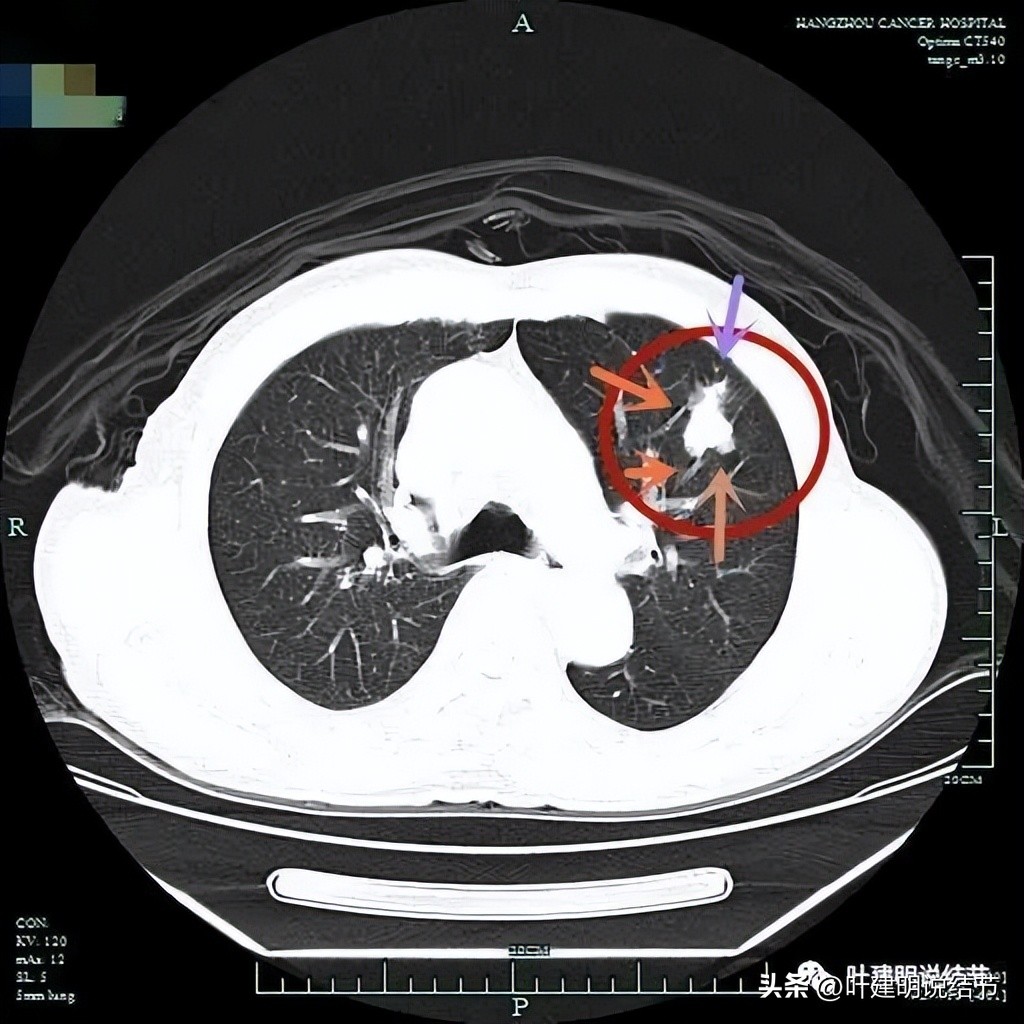

患者某C,女性,今年60岁,约1年前检查发现两肺多达15处以上的磨玻璃结节,分布于各个肺叶,其中右上叶最多,左下叶的最明显。而且还做过脑膜瘤手术,还有高血压等慢性病。下面这几处是左侧较为明显的病灶:

粉色圈起来的左上叶病灶(病灶A)密度低,但轮廓清楚,是肿瘤范畴的结节,但风险小;红色圈起来的左下叶结节(病灶B)虽然密度不太高,实性成分不明显,但它有多支微血管进入,而且紧贴胸膜,是要考虑微浸润性腺癌可能性为大的;蓝色圈起来的左下叶病灶(病灶C)是混合磨玻璃结节,但它的轮廓较为模糊,中间实性成分偏长方形,缺乏膨胀性或收缩力,磨玻璃部分密度过低,恶性的可能性虽有,但不如红色圈起来的病灶那么确定。而且与1年前对比,蓝色圈起来的这个病灶没有明显进展。此灶肉芽肿性炎的概率要高于恶性。